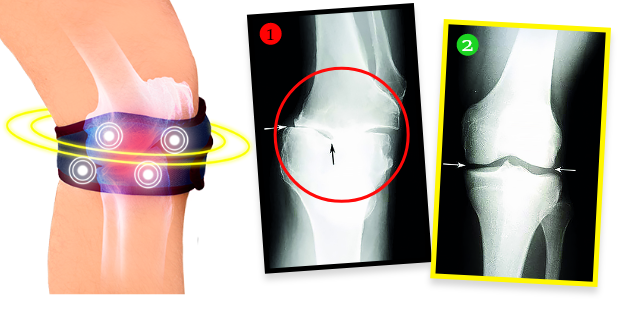

4 FÁZY PÔSOBENIA biomagnetického regeneračného pásu proti bolesti:

- Odstraňuje bolesť a stuhnutosť kĺbov už počas prvých 72 hodín nosenia

- Uvoľňuje a stabilizuje kĺby, urýchľuje procesy regenerácie chrupavky a obnovu synoviálnej tekutiny

- Znižuje svalové napätie, regeneruje tkanivá a spevňuje kĺbové štruktúry zvnútra, čím zvráti degeneratívne zmeny

- Hasí opuchy a zápaly, natrvalo odstraňuje zdroj bolesti

Pani Helena po ošetrení urobila röntgen a ukázalo sa, že degeneratívne zmeny v kolene sa úplne zvrátili! Doktor bol zarazený – nevedel, čo povedať. A fakty sú také, že vďaka biomagnetickému pásu sa nielenže stav kolena pani Heleny prestal zhoršovať. Chrupavkové tkanivo a jemné štruktúry v kĺbe sa zregenerovali a koleno sa vrátilo do plnej funkčnosti. Pás vyžaruje prirodzené a bezpečné biomagnetické pole, ktoré preniká do najhlbších tkanív kĺbu, vyživuje a regeneruje chrupavku, obnovuje jej elasticitu a tiež stimuluje tvorbu synoviálnej tekutiny, ktorá tlmí a chráni pred bolestivým trením pri pohybe. Je to úplne neinvazívna a bezpečná terapia.